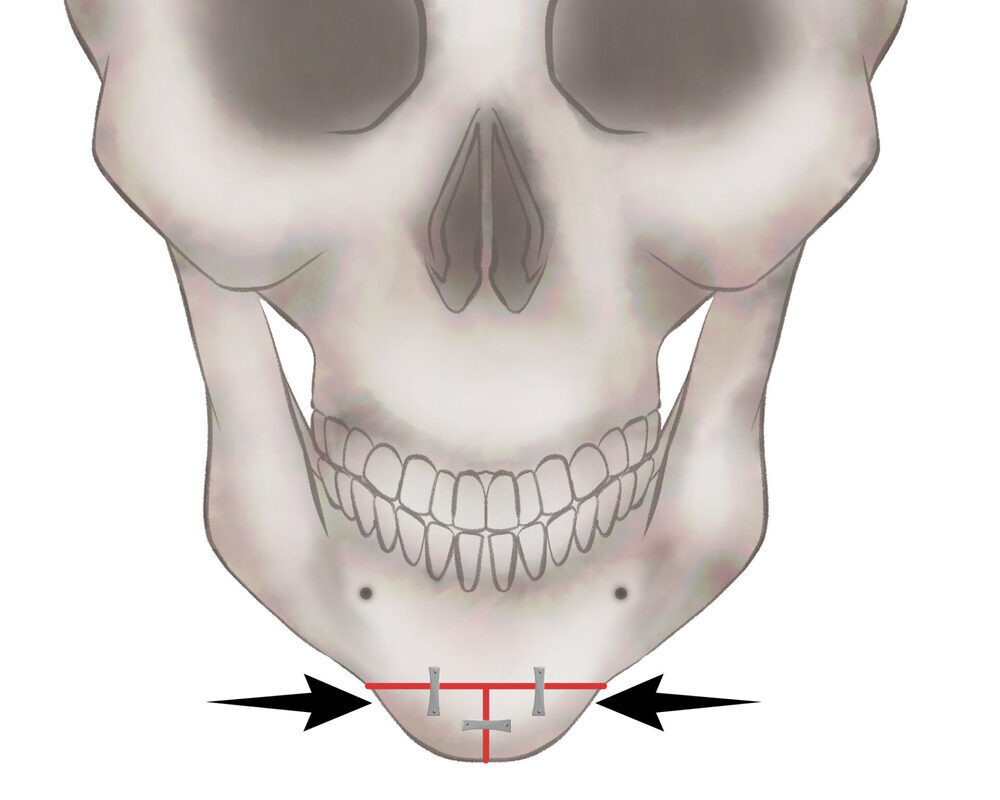

オトガイ骨切り(中抜き)

1.切開線をデザインします

2.骨を切除します

3.骨を移動させ段差を削ります

4.プレートで固定します